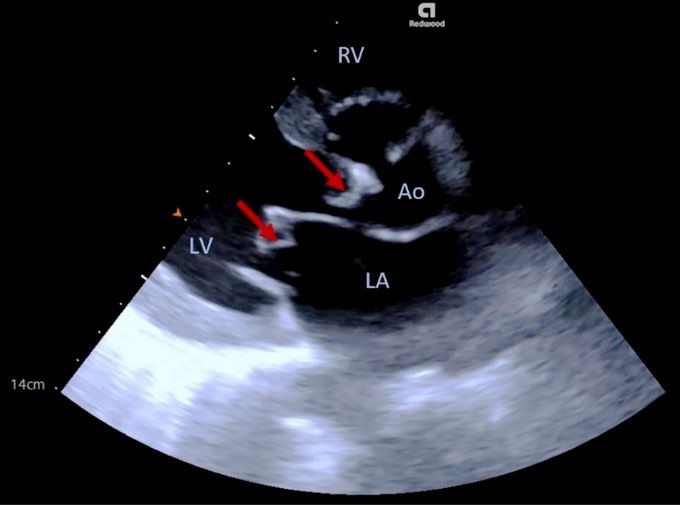

• Bedside Diagnosis of Double-Valve Endocarditis: A Rare Diagnosis

Cláudia Alves, Sara Barbosa, Sara Silva, Sheila Ferreira, José Mariz

91-94

DOI: https://doi.org/10.60591/crspmi.386